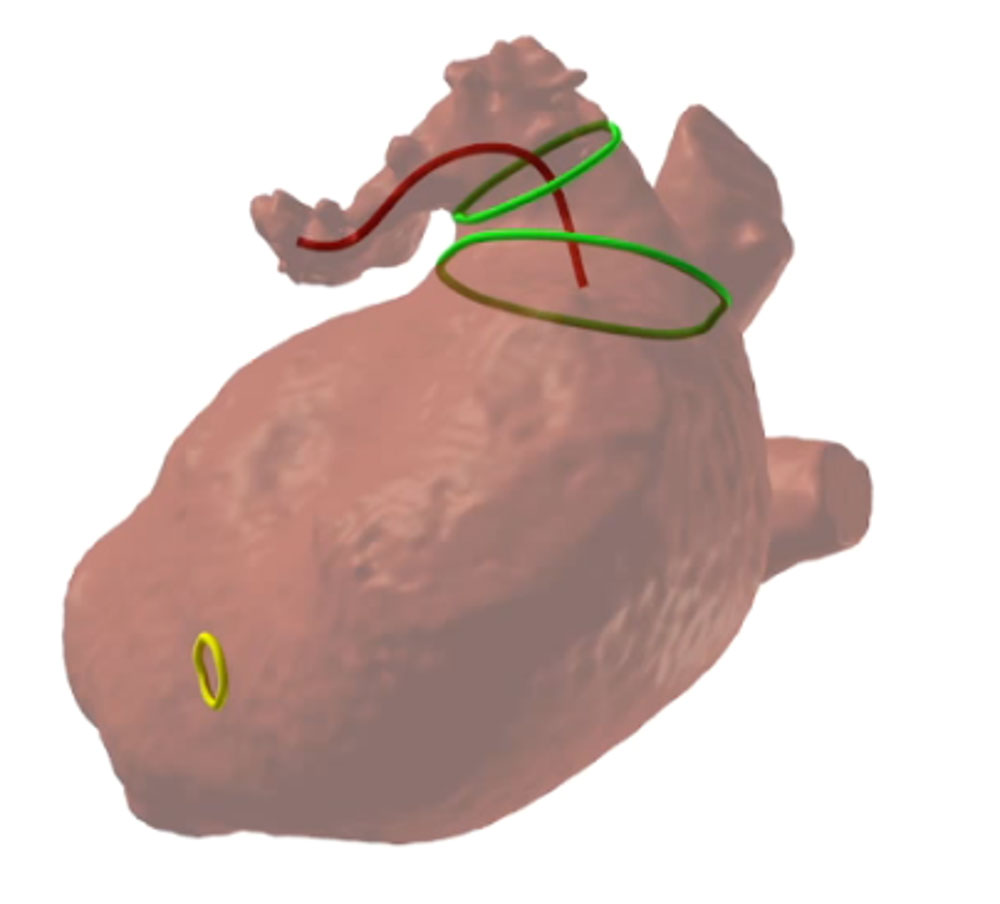

LAA closure - CT reconstruction

Min/max diameter: 22.0/25.9mm

Average diameter: 24.0mm

Area: 460mm2 (average 24.2mm)

Perimeter: 77.7mm (average 24.7mm)

Depth: 15mm

Diagnostic workup: cardiac CT reconstruction

- Cardiac CT allowed for reconstruction by FEops software modelling

- TOE was also available for pre-planning given the complex inferior chicken wing morphology

Given the elevated thromboembolic risk with paroxysmal atrial fibrillation and GI bleeding under DOAC, the decision was made to plan a left atrial appendage occlusion followed by dual antiplatelet therapy for 3 months. A CT and a TOE was performed in this case for planning the procedure, as CT revealed a challenging morphology for both single- and double-disc devices with a shallow LAA (15mm depth) and an inferior-bend chicken wing morphology.